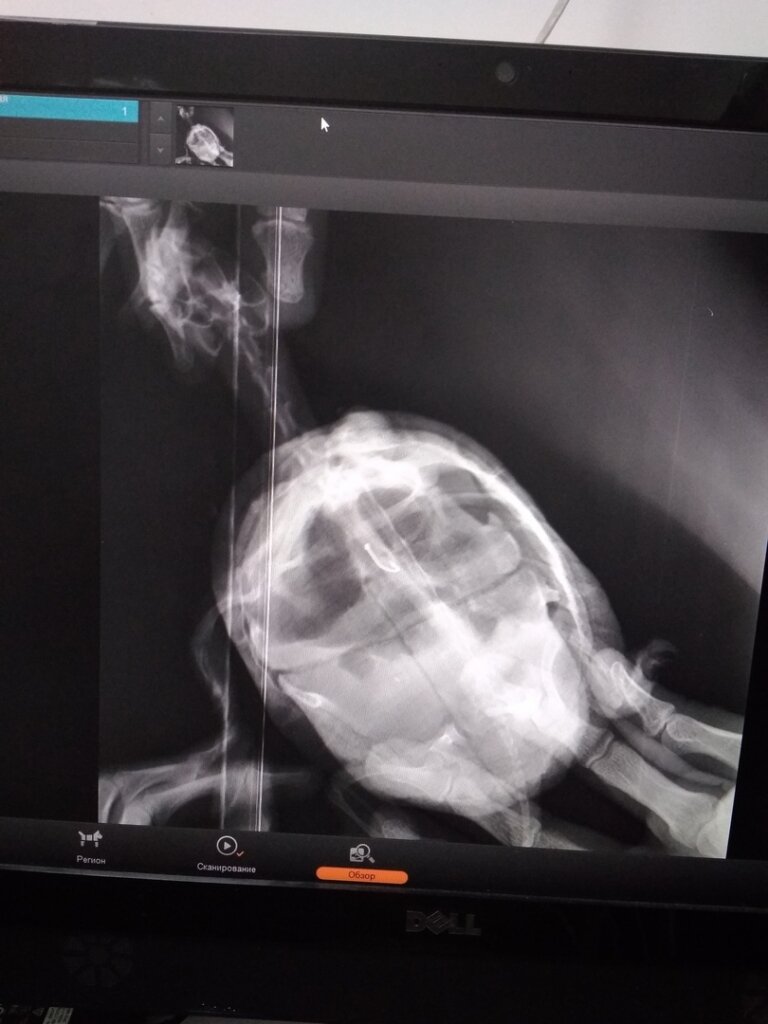

Одно животное местные жители нашли с крючком во рту и отнесли к ветеринару В ветеринарной клинике нам рассказали, что животное с крюком в желудке не сможет долго прожить, нужно обязательно его доставать.

Но эта процедура обойдется в 12 тысяч рублей.

Одно животное местные жители нашли с крючком во рту и отнесли к ветеринару

В ветеринарной клинике нам рассказали, что животное с крюком в желудке не сможет долго прожить, нужно обязательно его доставать.